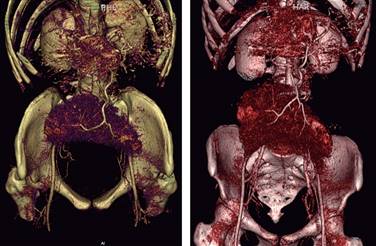

El cuadro clínico cuando se presenta sintomático suele ser inespecífico, por lo que los estudios imagenológicos juegan un importante papel en el diagnóstico y de sus complicaciones. La tomografía abdominal contrastada es considerada el mejor estudio, aunque también pudiera ser útil el ultrasonido de abdomen. A menudo se identifica por su forma característica de “coma”, sin observar el bazo en el cuadrante superior izquierdo; seguir el trayecto de los vasos esplénicos puede ayudar a identificar correctamente el bazo errante (Figuras 2 y 7).2

Figura 7: Tomografía abdominopélvica contrastada en reconstrucción 3D, se observa el trayecto de la arteria esplénica.